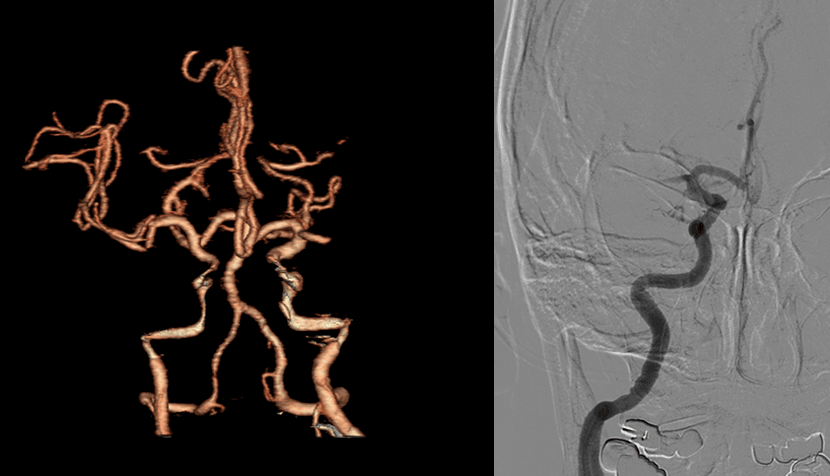

수술전 뇌CT 영상에서 뇌지주막하출혈 소견이 보임

CT 혈관조영술상 뇌동맥류 발견

뇌혈관조영술로 동맥류에 대해 정밀검사

혈관내 코일색전술을 통해 개두술 없이 동맥류를 치료함